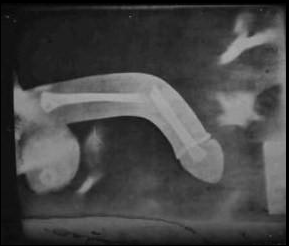

Voici la photo de la radio de l'op https://image.noelshack.com/fichiers/2023/13/5/1680299240-fractureloptesfinito.png https://image.noelshack.com/fichiers/2018/25/2/1529422413-risitaszoom.png

Stop le fake j'ai vu la même à Castorama rayon robinetterie https://image.noelshack.com/fichiers/2018/13/4/1522325846-jesusopti.png